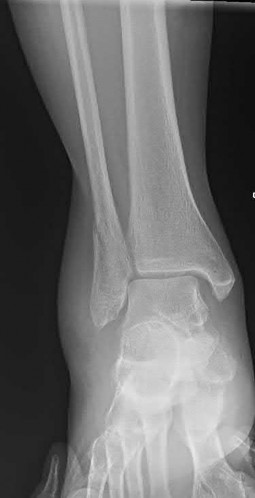

A 64-year-old woman is thrown off a horse, sustaining the injury shown in Figures A and B. She undergoes surgical fixation as seen in Figures C through E. What is the most commonly reported complication of this procedure?

The patient in the scenario has a 2-part proximal humerus fracture treated with a locking plate as seen in Figures A-E. The most common complication with the use of this implant is screw penetration. The terms screw cut out and penetration are often used interchangeably in the literature with cut out appearing more frequently in reports regarding intertrochanteric fractures.

Owsley et al retrospectively reviewed 53 proximal humerus fractures treated with locking plates and the same post-operative protocol. The most common complication was screw cut out or penetration, followed by varus displacement. They concluded that 3 and 4-part fractures in patients over 60 years have a higher incidence of failure.

Agudelo et al retrospectively reviewed 153 patients at a level-one trauma center treated with proximal humerus locking plates, investigating modes of failure for the implant. They determined that varus malreduction (head-shaft angle